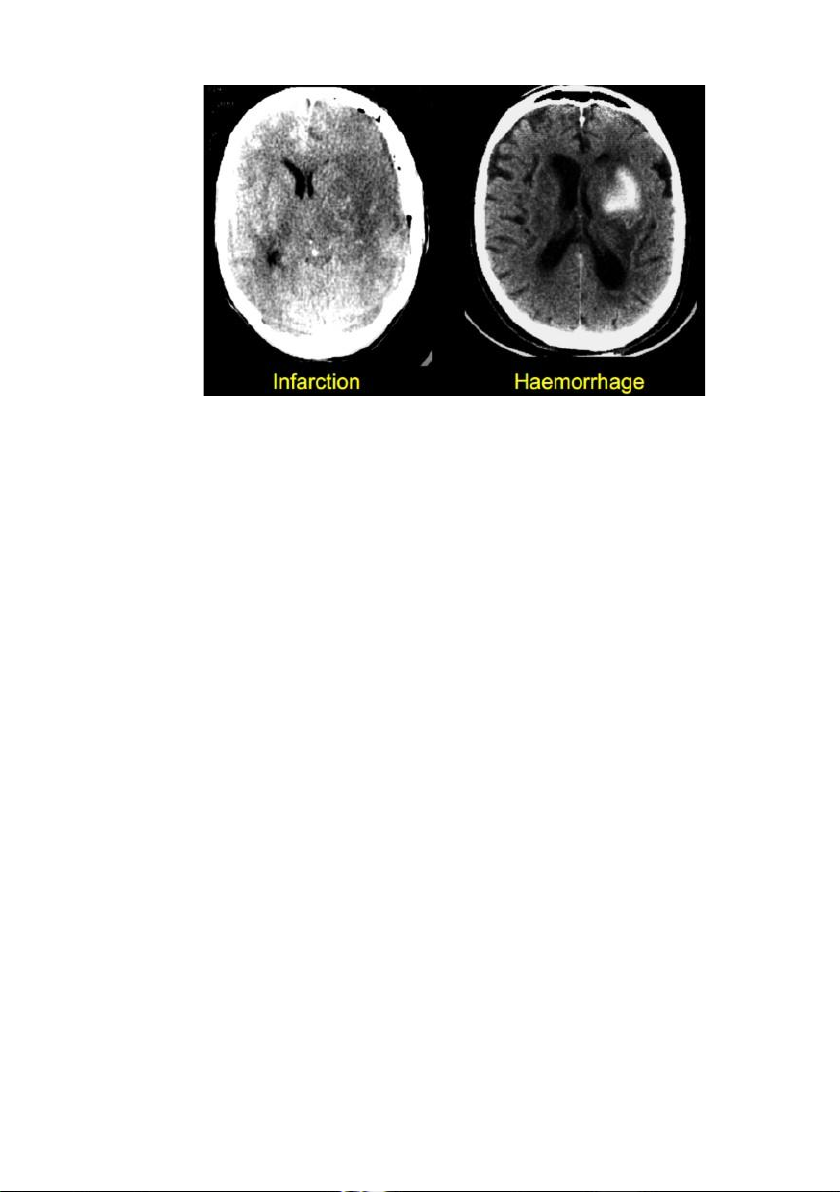

Đột quỵ xảy ra có thể do thể nhồi máu não hoặc chảy máu não.

1.4.1. Nhồi máu não:

Xảy ra khi một mạch máu não bị tắc hoặc nghẽn, làm cho vùng

não bị thiếu máu (đột quỵ thiếu máu cục bộ) và dẫn đến hoại tử

(nhồi máu). Loại tai biến này chiếm 80%. Trong nhóm đột quỵ

do nhồi máu não, 50% là do xơ vữa động mạch, 25% là do bệnh

các mạch máu nhỏ trong não (nhồi máu ổ khuyết), 20% là do

thuyên tắc từ tim, 5% c n lại do những nguyên nhân hiếm gặp.

1.4.2. Chảy máu não:

Xảy ra khi mạch máu bị vỡ, máu chảy vào nhu mô não và các não

thất. Loại tai biến này chiếm 20% (15% chảy máu trong não- liên

quan đến huyết áp cao và dị dạng động tĩnh mạch; 5% chảy máu

dưới nhện- liên quan đến vỡ phình động mạch não).

Chảy máu não thường có biểu hiện rất cấp tính, rầm rộ, toàn thể,

có thể gây rối loạn ý thức nhanh, hôn mê và tử vong do đó cần

phải xác định sớm bằng xét nghiệm hình ảnh học (CT cấp cứu). lOMoAR cPSD| 45470709

Nhồi máu não chảy máu não

Hình 1. Hình ảnh CT của đột quỵ